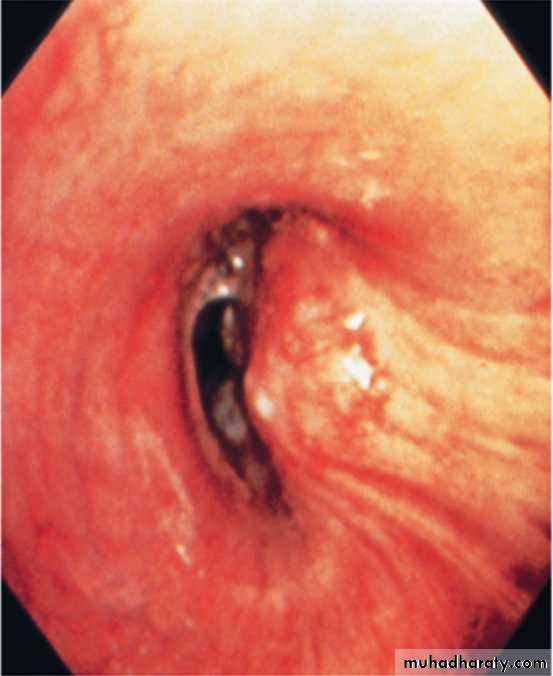

2-Flexible bronchoscope; The tumour is visualized directly. Bronchial biopsies and brush samples can be taken. It is useful for proximal lesion (near to large airway).

Lung cancer visualized by bronchoscopy, the tumour protruding from bronchial wall to the lumen